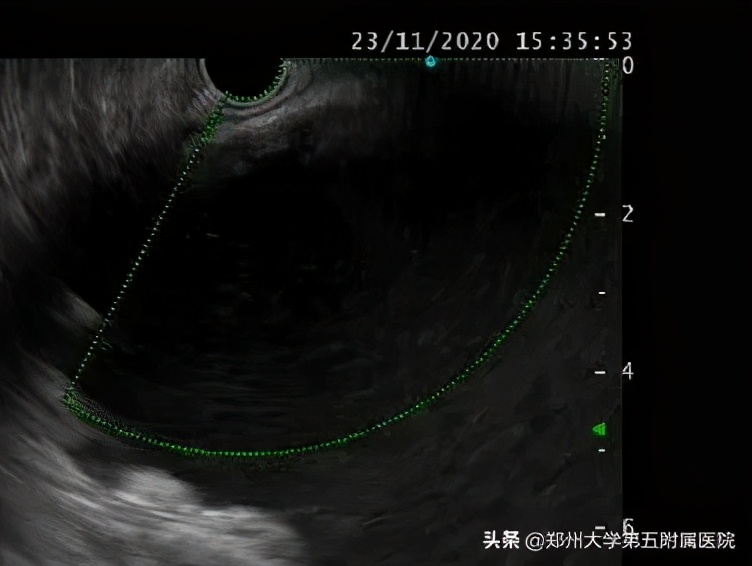

在消化内镜中心主任郑权指导下,刘谦副主任医师先行超声胃镜检查,以确定囊肿的位置,大小,是否适合超声下穿刺置管引流,超声内镜显示囊肿15+cm,囊壁与胃壁距离小于1cm,病灶毗邻胃后壁,胃腔严重受压。在超声内镜引导下成功穿刺进囊肿,切开囊肿壁,大量脓液流出,囊肿明显缩小,后置入双猪尾支架和鼻囊肿引流管结束手术,术中引流囊液约1000ml。

▲ 超声内镜图见巨大囊肿及囊液